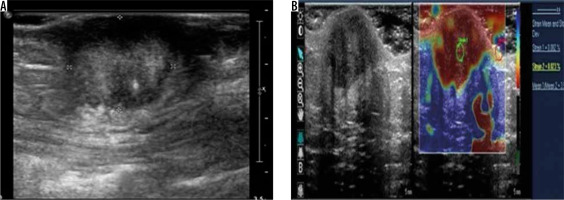

Figure 8

Anterior abdominal wall endometrioma – greyscale ultrasound image (A) shows a well-defined, round, hyperechoic lesion seen in the subcutaneous plane. Strain elastography (B) of the same lesion depicts it predominantly in red colour on an elastography map and a strain ratio of 3.57 suggesting the “hard” nature of the lesion. However, the lesion turned out to be endometrioma on histopathology